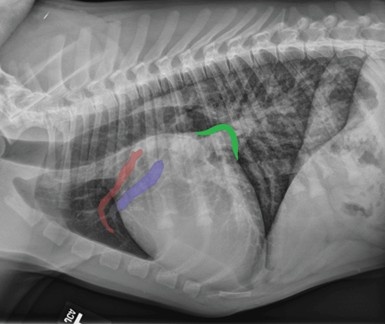

3. Congenital Heart Disease

Source: TodayVeterinaryPractice

There have been various studies of congenital heart disease in dogs refers to heart defects present at birth, not a form of canine Down syndrome. While dogs cannot have Down’s syndrome due to fundamental chromosomal differences, they can have conditions that present similar symptoms. These abnormalities develop during fetal growth and can severely impact your dog’s quality of life. Many pet owners mistake these cardiac issues for a Down syndrome-like condition because of similar physical and behavioral symptoms.

The connection between congenital heart disease and Down syndrome-like appearances stems from the fact that both conditions can cause developmental issues. In humans, Down syndrome patients frequently have heart defects (40-50% of cases), creating a similar pattern of symptoms that people sometimes project onto their pets.